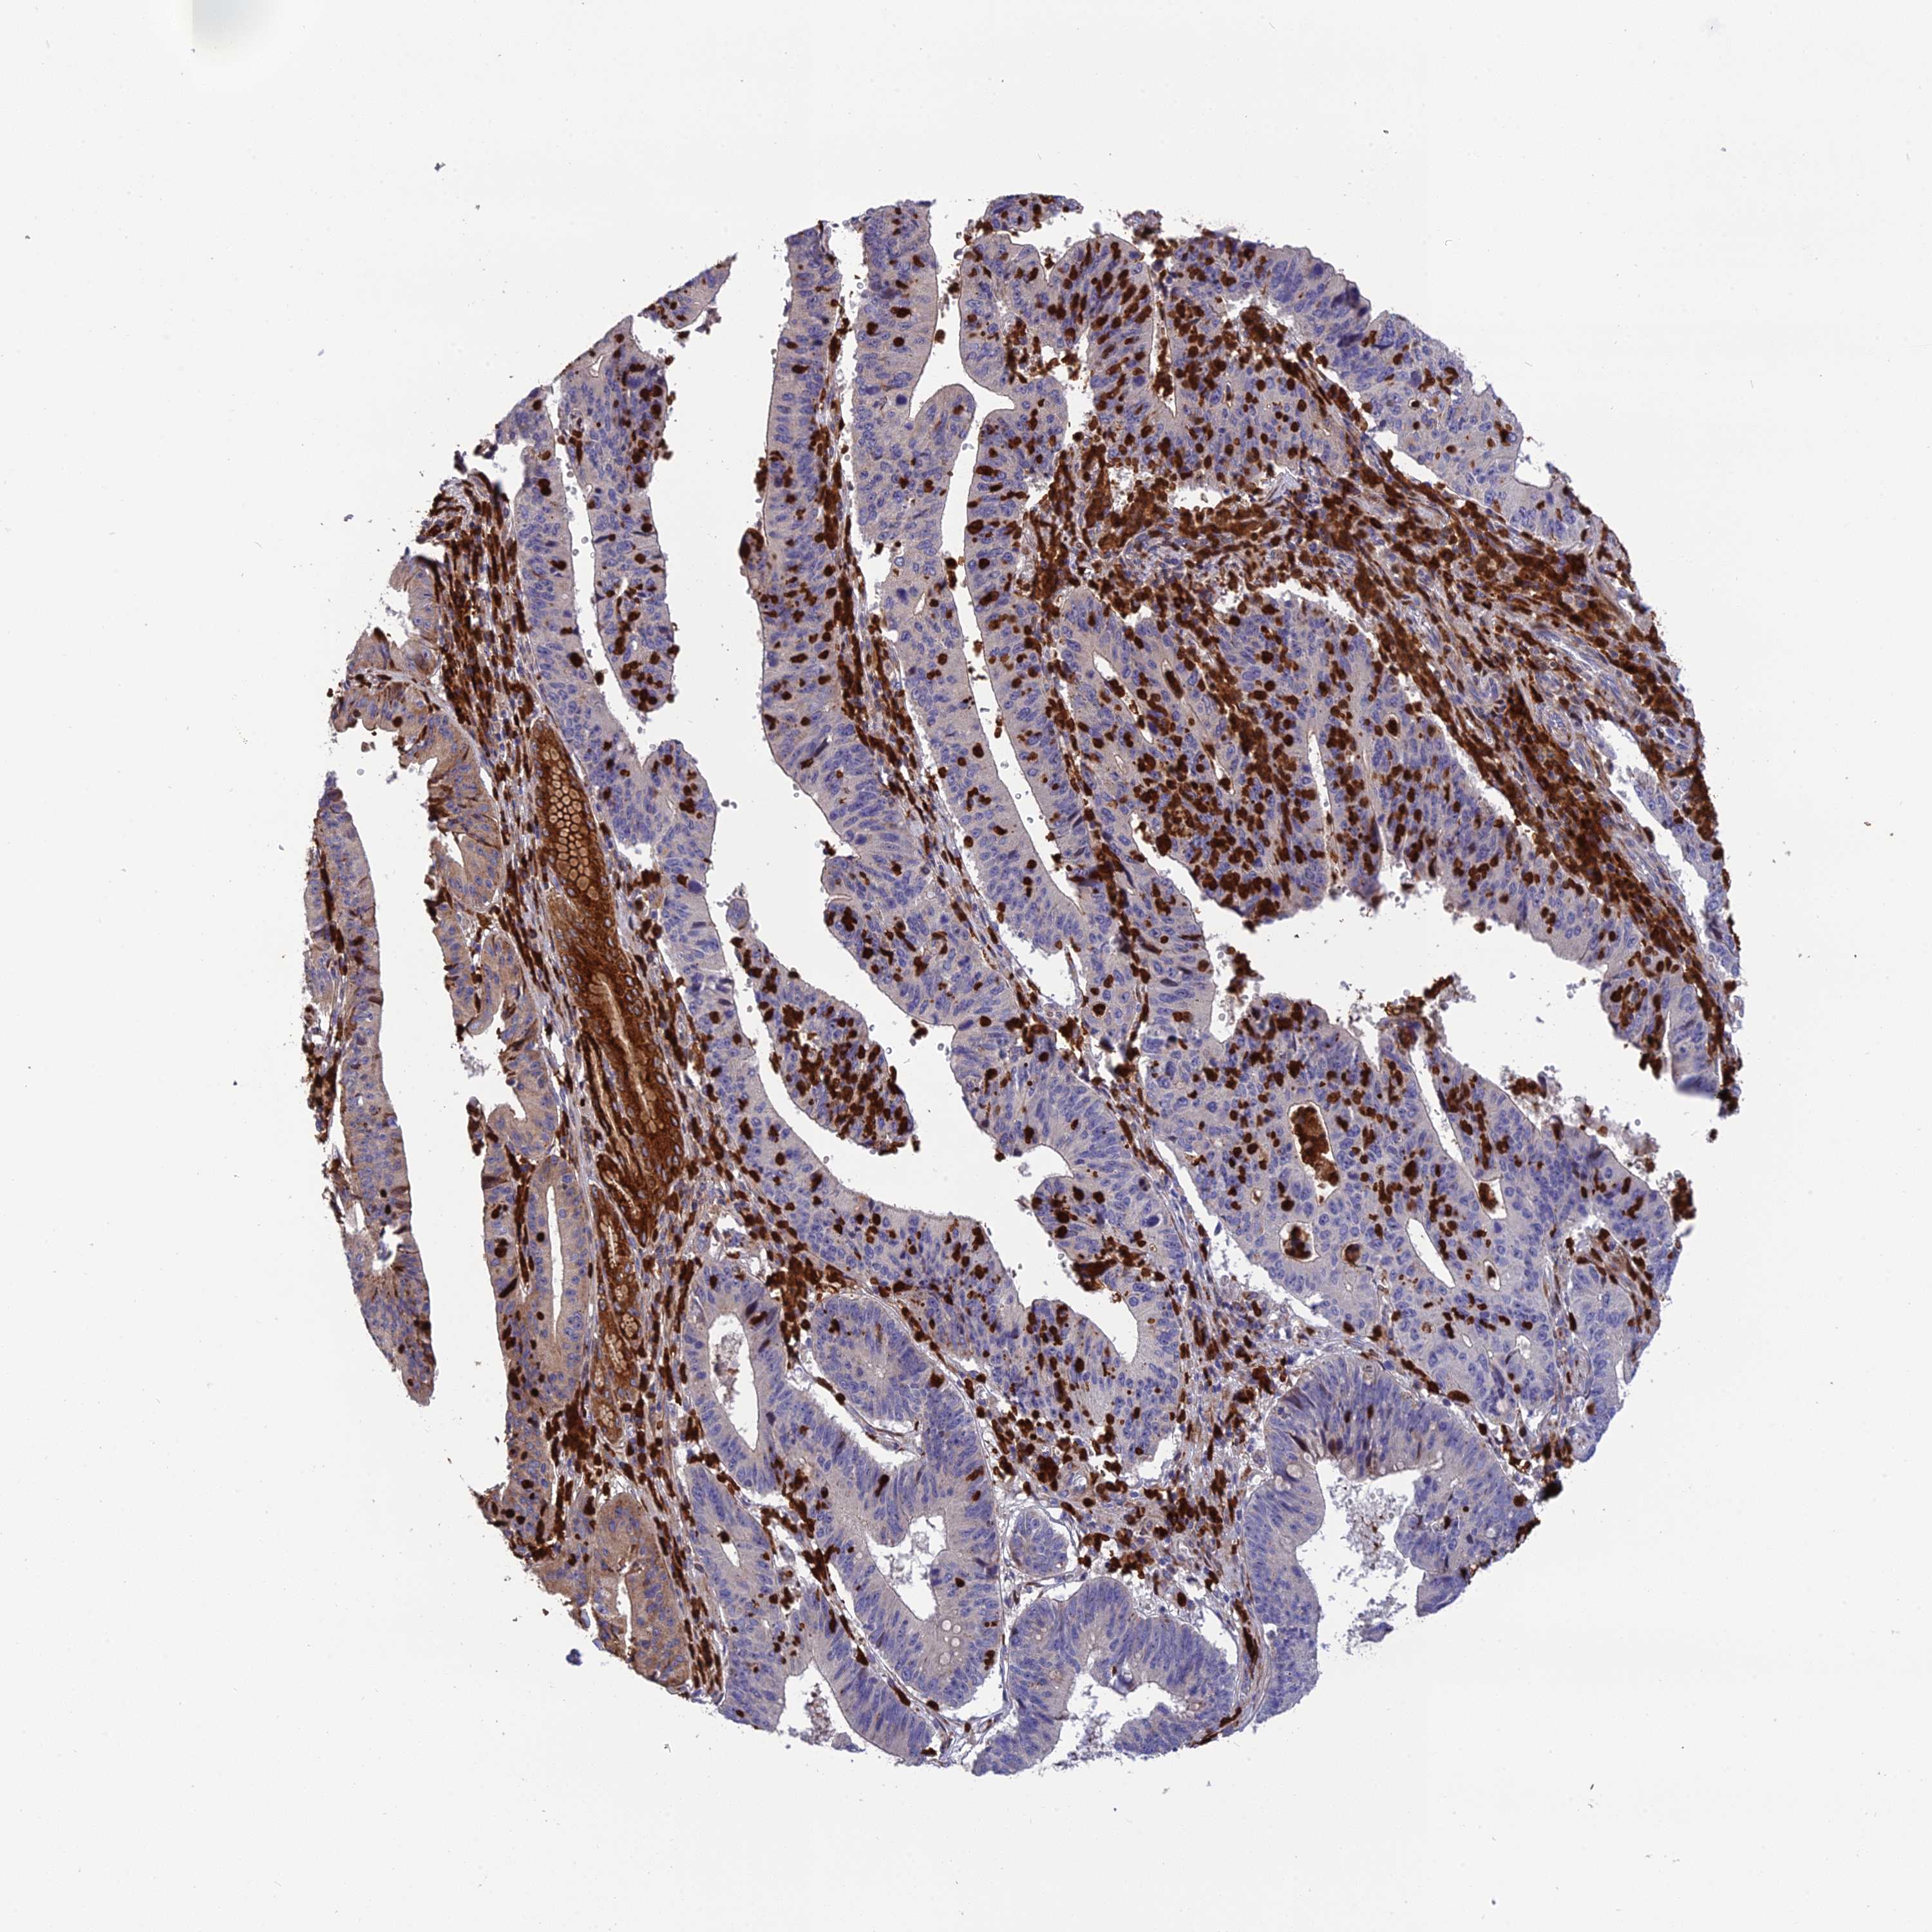

STOMACH CANCER - Protein expressioni

A mouse-over function shows sample information and annotation data. Click on an image to view it in a full screen mode. Samples can be filtered based on level of antibody staining by selecting one or several of the following categories: high, medium, low and not detected. The assay and annotation is described here.

Note that samples used for immunohistochemistry by the Human Protein Atlas do not correspond to samples in the TCGA dataset.

Antibody stainingi

Antibody staining in the annotated cell types in the current human tissue is reported as not detected, low, medium, or high, based on conventional immunohistochemistry profiling in selected tissues. This score is based on the combination of the staining intensity and fraction of stained cells.

Each image is clickable and will lead to virtual microscopy that enables deeper exploration of all samples and also displays staining intensity scores, fraction scores and subcellular localization as well as patient and tissue information for each sample.

Antibody HPA044047

Staining

High

Medium

Low

Not detected

Intensity

Strong

Moderate

Weak

Negative

Quantity

>75%

75%-25%

<25%

None

Location

Nuclear

Cytoplasmic/membranous

Cytoplasmic/membranous,nuclear

Adenocarcinoma, NOS